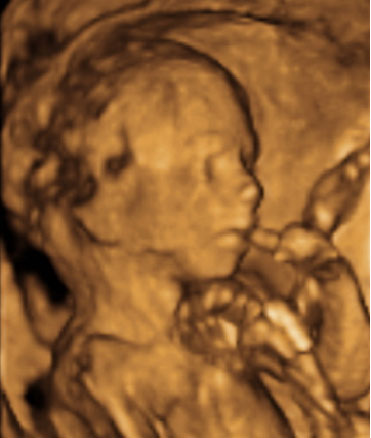

Día a día el feto se va poniendo más hermoso. Su cara se va acercando poco a poco a la de un bebé a término: Ya cuenta con cejas y pestañas, aunque sus párpados aún permanecen cerrados.

"Los párpados son simples repliegues cutáneos. en un principio están soldados el superior y el inferior, hasta el séptimo mes de gestación". Dr. José Manuel Ramírez Sebastián, Director del Instituto Investigaciones Oftalmológicas Ramón Castroviejo.

"En diferentes ecografías a veces se detecta desde muy pronto la posición de las manos del bebé en su cara o introduciendo los dedos en su boca. Es tacto/contacto propiamente dicho, ya que desde tan temprano el feto conoce y se reconoce a través de diferentes formas de tocarse. No es entonces una novedad que nos toquemos diariamente entre 500 y 800 veces al día sin tener consciencia de ello. ¡Comenzamos muy pronto, desde el útero materno!".

Elsa Rodríguez, Formadora Internacional de International Association of Infant Massage (IAIM)